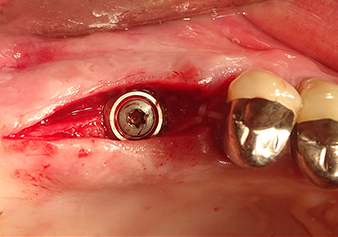

После промежуточного контроля (рис. 4) был проведен еще один этап подготовки (рис. 5). За тем, с помощью гидравлического инструмента Z35P мембрана была поднята в нужное положение (рис. 6 и 7). Далее, следовала дальнейшая пьезохирургическая подготовка ложа для имплантата, завершенная с помощью ротационного бора и лопаточной фрезы до диаметра имплантата 4,8 мм. Перед установкой имплантата под мембрану Шнейдера был введен аугментационный материал (размер частиц около 0,8-1,6 мм) (рис. 8).

Имплантация и протезирование

Для перемещения аугментационного материала в направлении верхнечелюстной пазухи атравматично, имплантат вводился очень медленно вручную (рис. 9). При этом мембрана еще раз выталкивалась в краниальном направлении. Через два месяца место операции зажило без раздражения. Через шесть месяцев рентгеновский контроль показал значительное увеличение помутнения, что свидетельствует об оссификации (рис. 10). Протезирование было проведено металлокерамической коронкой.